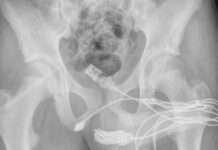

İngiltere’de 15 yaşındaki çocuk cinsel organında öyle bir şey denedi ki, tıp literatürüne girdi…

İngiltere'de 15 yaşındaki çocuk cinsel organında öyle bir şey denedi ki, tıp literatürüne girdi...

İngiltere’de yaşayan 15 yaşındaki bir çocuğun cinsel tatmin için denediği yöntem...